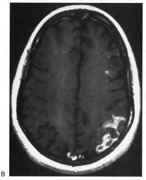

Fig. 15. Bilateral incomplete hemianopia. A 69-year-old man with decreased vision after prostate surgery. A. Fields show remaining central parafoveal vision with some sparing of inferior left quadrant. Note how the defect respects the vertical meridian. B. MRI shows bilateral medial occipital infarction, with sparing of the occipital poles, accounting for the macular-sparing bilaterally. (Courtesy of Dr. Lucia Vaina.)